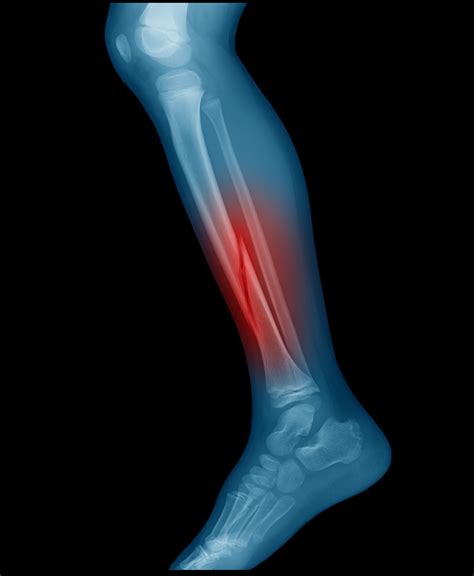

Symptoms You Should Not Ignore

Recognizing the symptoms of a leg fracture early is vital for preventing complications such as nerve damage or compartment syndrome. If you experience an injury, look for the following signs:

Immediate symptoms include:

• Intense, sharp pain that worsens with movement.

• Visible deformity or an unnatural angle of the limb.

• Inability to bear weight on the affected leg.

• Significant swelling, bruising, or tenderness around the injury site.

• Numbness or tingling in the foot, which may indicate nerve impairment.

Diagnostic Procedures

If you suspect you have sustained fractures of the leg, immediate medical attention is necessary. Doctors typically utilize advanced imaging to determine the exact location and complexity of the break:

Diagnostic Tool Purpose

X-rays The primary method for identifying breaks and alignment issues.